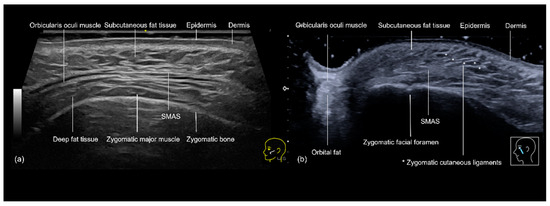

3.4. Zygomatic and Preauricular Region

3.4.1. Sonographic Anatomy of the Zygomatic and Preauricular Region

3.4.2. Ultrasound-Guided Filling Techniques of the Zygomatic and Preauricular Region

- Zygomatic Region

- Technique 1: Supraperiosteal filler placement

- Technique 2: Subcutaneous filler injection